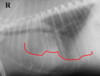

If you see a “bow-legged cowboy sign” on a DV view, what is your DDx?

left atrial enlargement